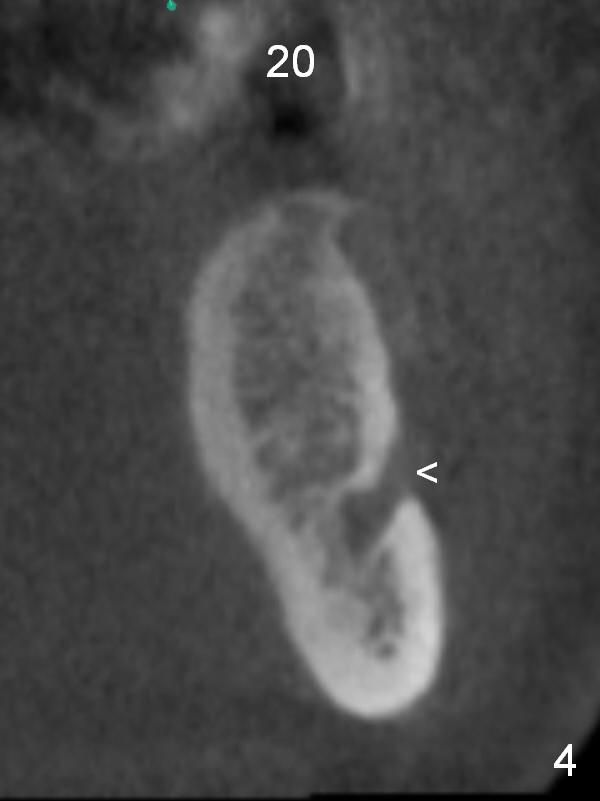

A 39-year-old man is pleased with implant placement at the lower right premolars (Fig.1: #28,29). He wants to have the same treatment at the lower left (#20,21), although the neighboring teeth need more urgent treatment. CBCT coronal sections at #21 (Fig.2) and 20 (Fig.4) show that the crest at the 1st premolar is particularly narrow and pointed. Since the Mental Foramen is at the 2nd premolar (arrowhead in Fig.4, 6 (sagittal section)), it seems appropriate to resect the atrophic crest by 6-7 mm at #21 (Fig.3 black area) and place a narrow implant low. It may invade the Incisive Nerve (Fig.7 brown cicle), which should be insignificant. A long abutment is expected at #21. A regular implant and abutment are expected at the 2nd premolar, similar to the right side. Smaller implants may be more appropriate (3.8 mm) to reduce postop bone resorption. In fact, the patient cracks the tooth #31. It seems to be nonsalvageable. In fact, what is to be done?